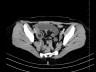

Case of the Week 25 2016 *39-year-old female with abdominal pain and vomiting. What is the most likely diagnosis? Answer Answer: Small bowel obstruction caused by intussusception produced by an ileal lipoma. Kategori:Cases Önceki yazı Case of the Week 21 2016 Sonraki yazı Case of the Week 26 2016